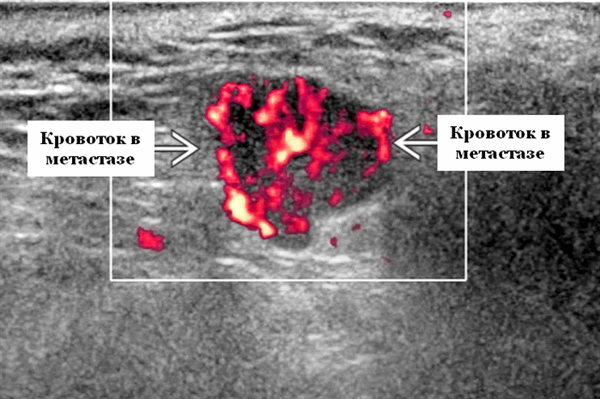

- Интранодулярный кровоток хаотичный / дезорганизованный или преимущественно периферический

Энергетический допплер. Внутриочаговая васкуляризация. Хаотический / дезорганизованный или преимущественно периферический кровоток